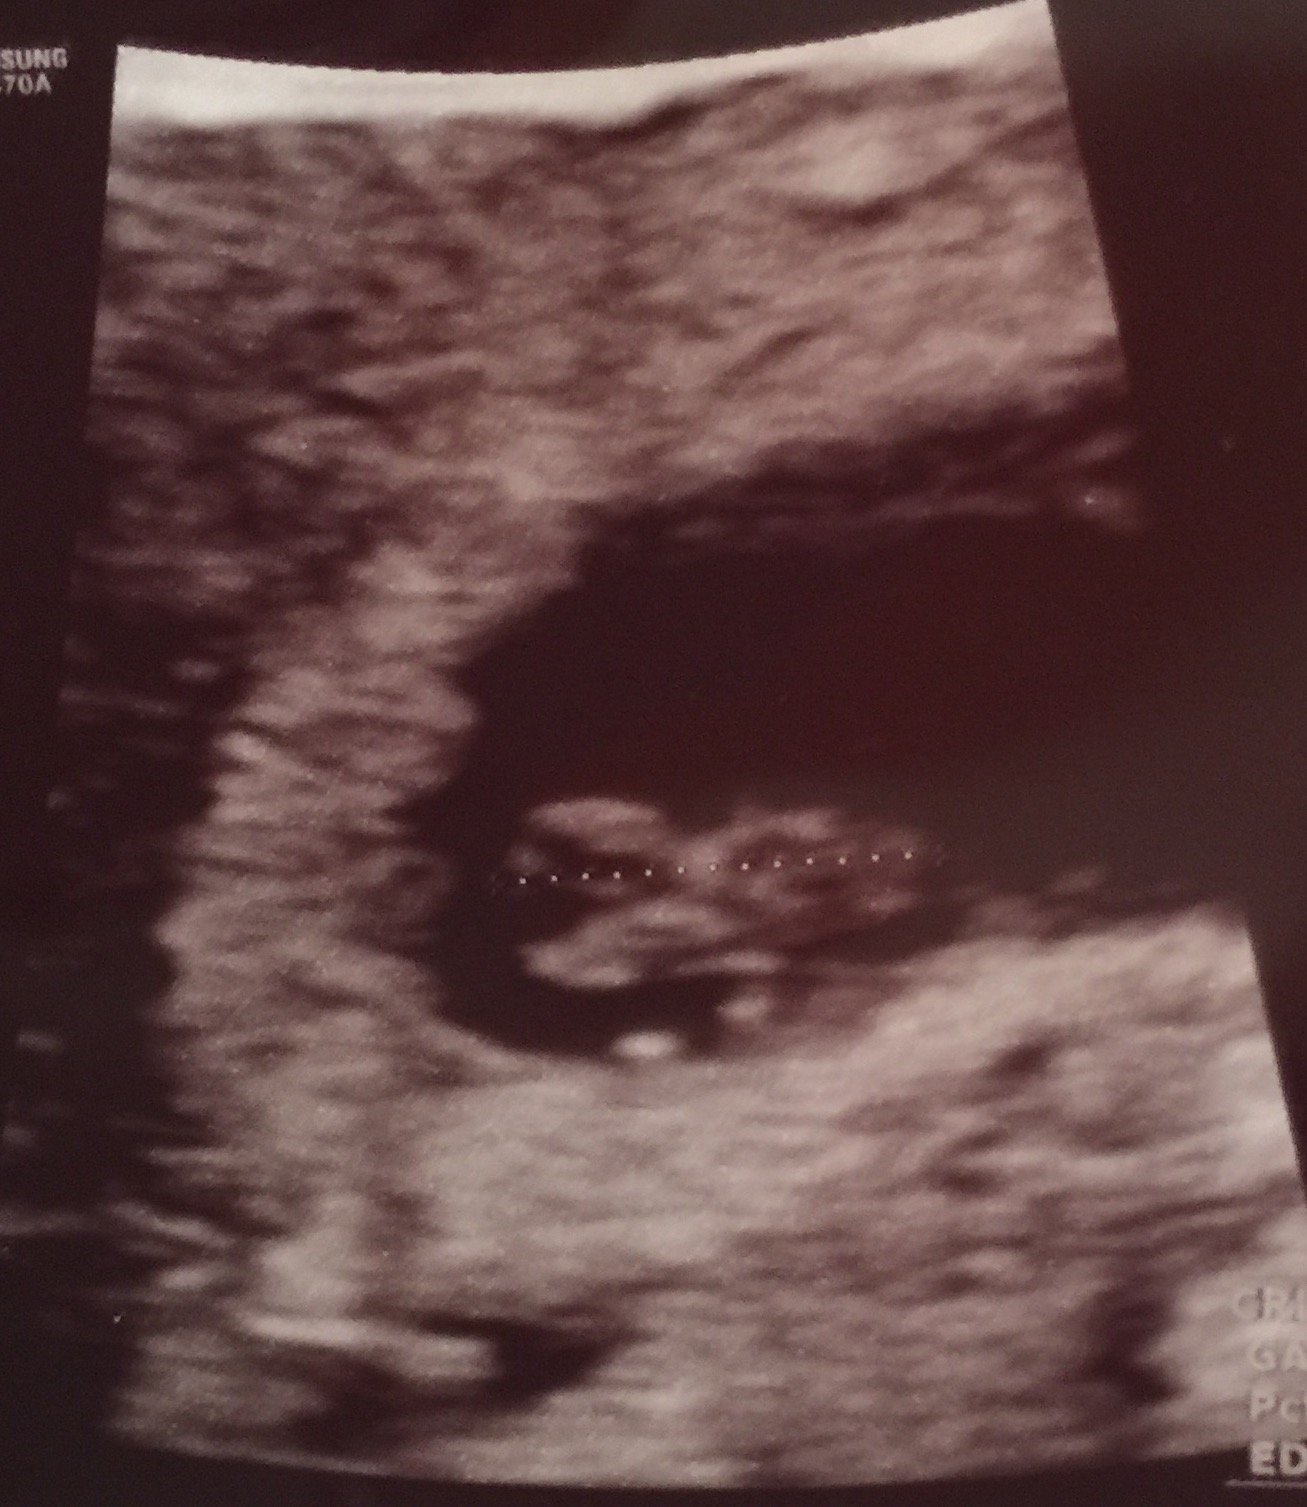

I had my third U/S on Friday. I was exactly 9 weeks. Baby measured right on track for 1/5 due date and had a heart rate of 182. My doctor was super pumped! You can even see baby's little arms and legs. Legs are to the left, head is to the right, little belly in the middle, and then a little arm sticking up. So cute!

Baby at 9 weeks. Measuring right on track and a healthy heartbeat. Baby was wiggly during the ultrasound.